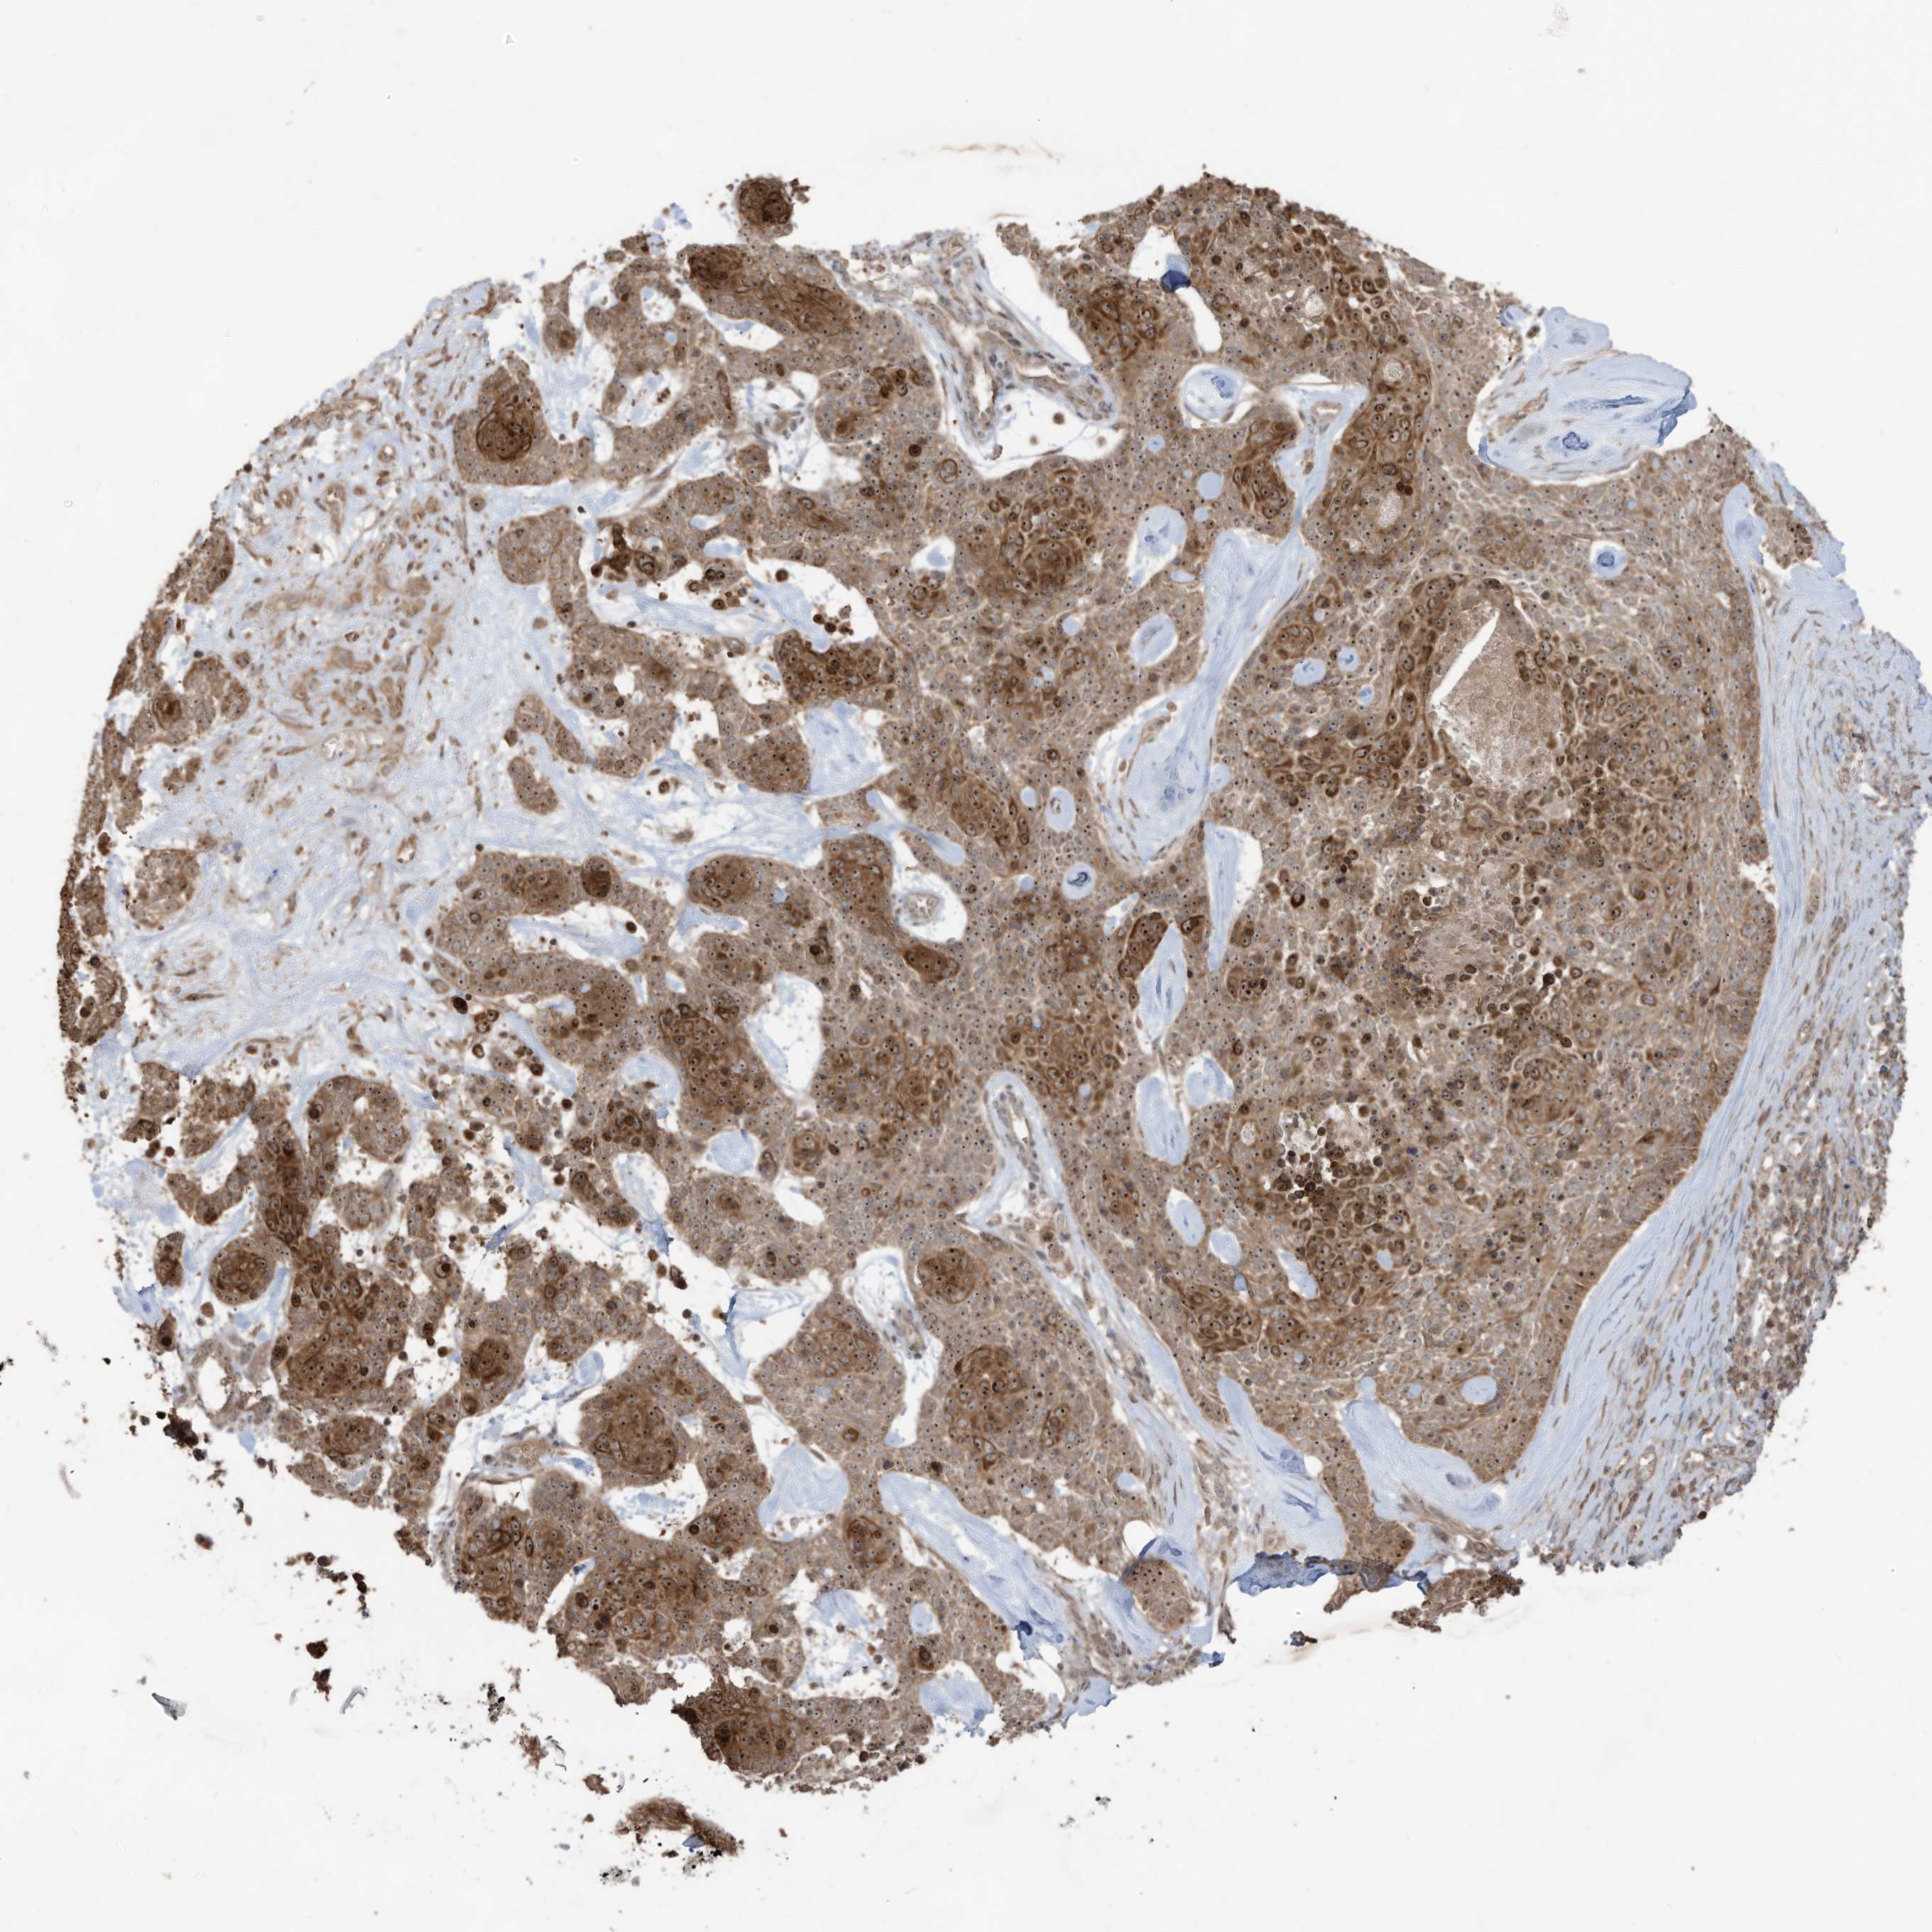

SKIN CANCER - Protein expressioni

A mouse-over function shows sample information and annotation data. Click on an image to view it in a full screen mode. Samples can be filtered based on level of antibody staining by selecting one or several of the following categories: high, medium, low and not detected. The assay and annotation is described here.

Each image is clickable and will lead to virtual microscopy that enables deeper exploration of all samples and also displays staining intensity scores, fraction scores and subcellular localization as well as patient and tissue information for each sample.

Antibody HPA034557

Staining

High

Intensity

Strong

Quantity

>75%

Location

Nuclear

Squamous cell carcinoma, NOS